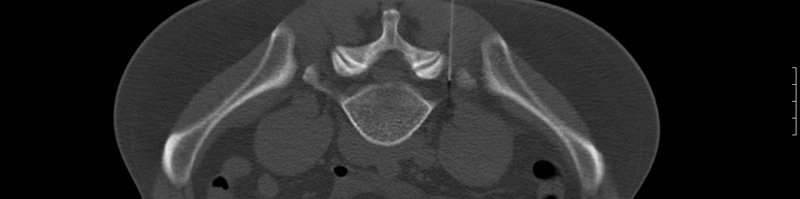

CT-gesteuerte Interventionen

Aus personellen Gründen können wir diese Leistungen ab dem 01.01.2023 nicht mehr anbieten.